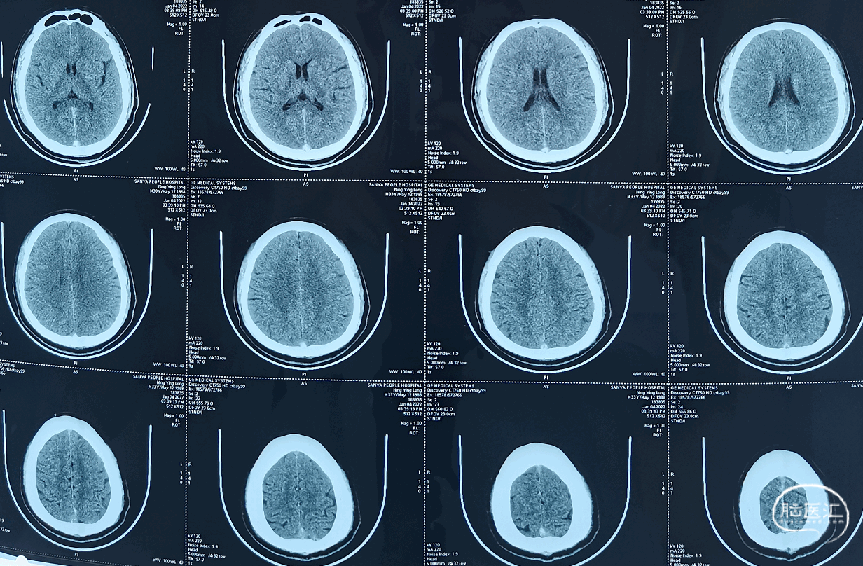

头颅CT(2022-1-10)

术后复查头颅CT(2022-1-15)